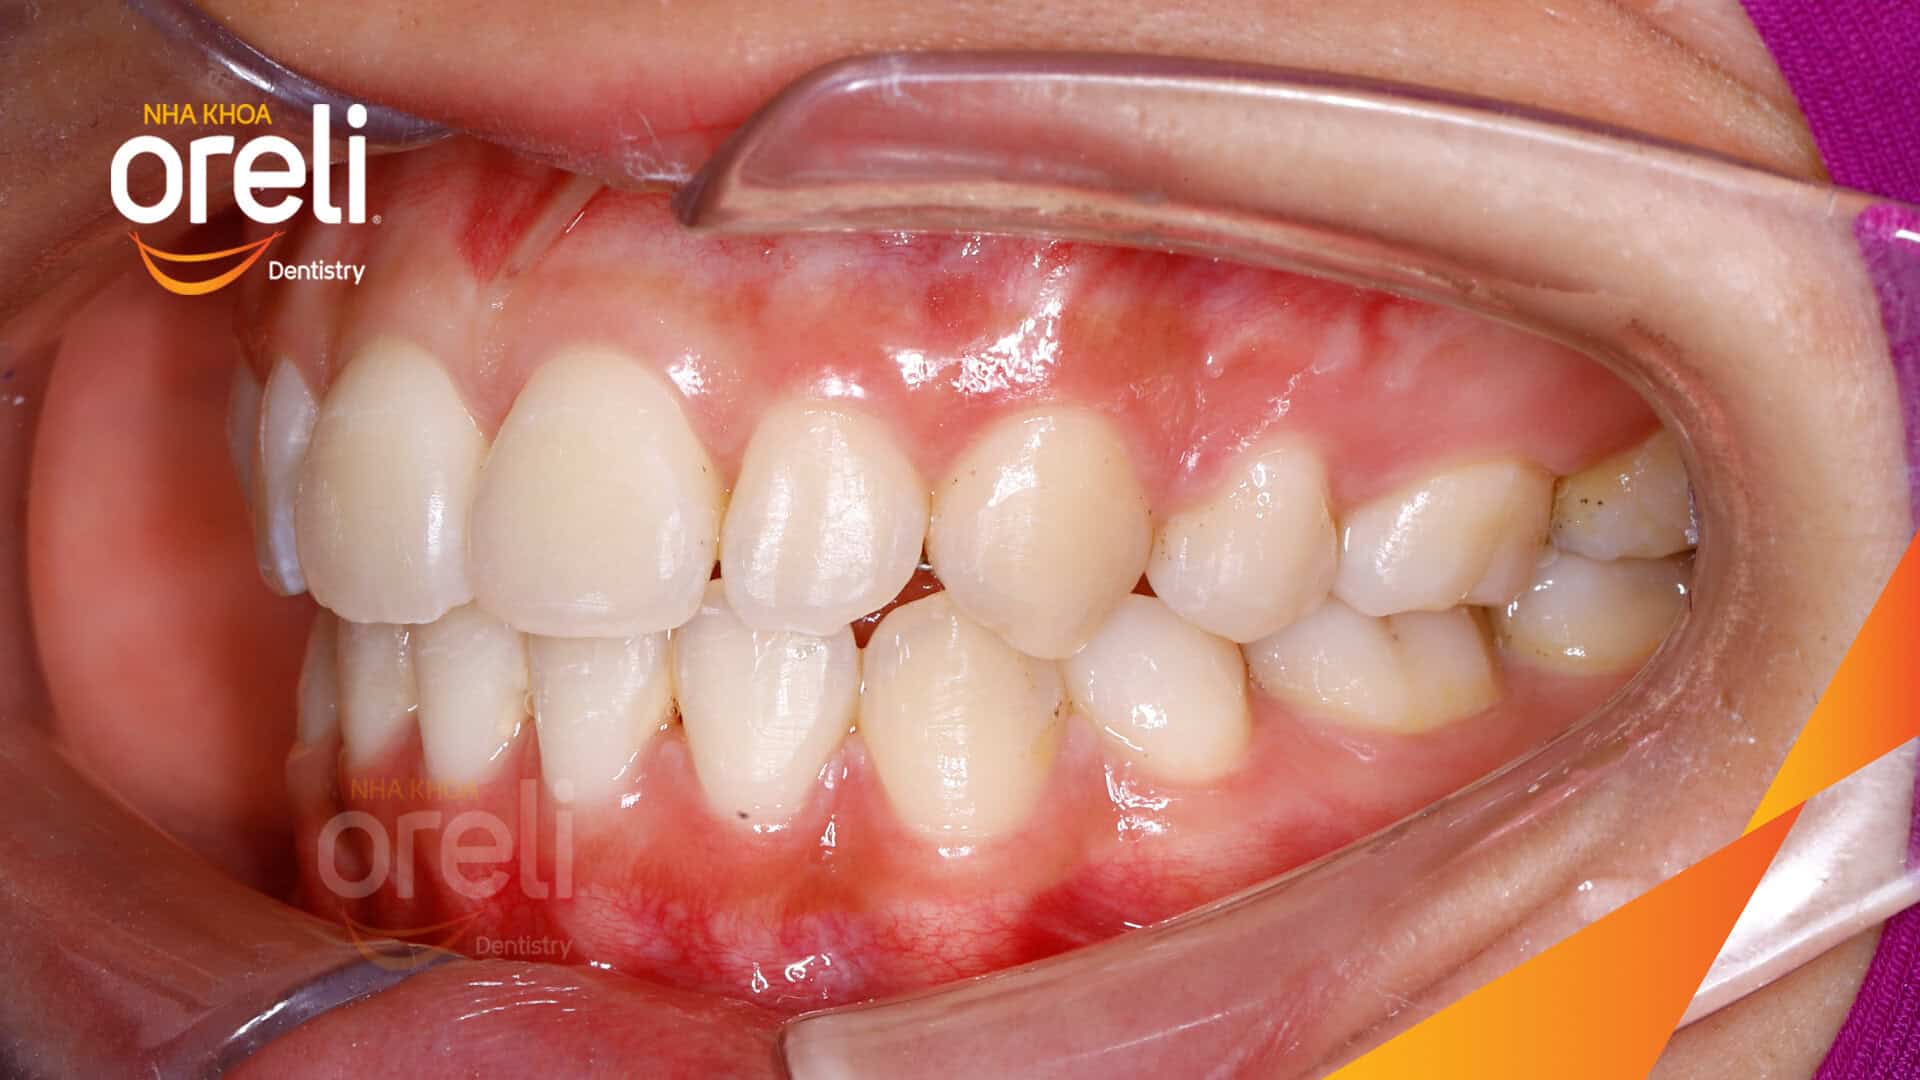

Tình trạng: Răng hô nhô xương ổ hai hàm

Kết quả: Khớp cắn đúng nụ cười tự nhiên, góc mặt nghiêng đẹp

Trong trường hợp này độ nhô môi lớn, góc mũi môi nhọn, môi trên và dưới trượt ra trước so với đường thẩm mỹ E của Rickket, trục răng cửa hàm trên ngả trước nhiều. Việc nhổ răng 4 để giảm hô được thực hiện.